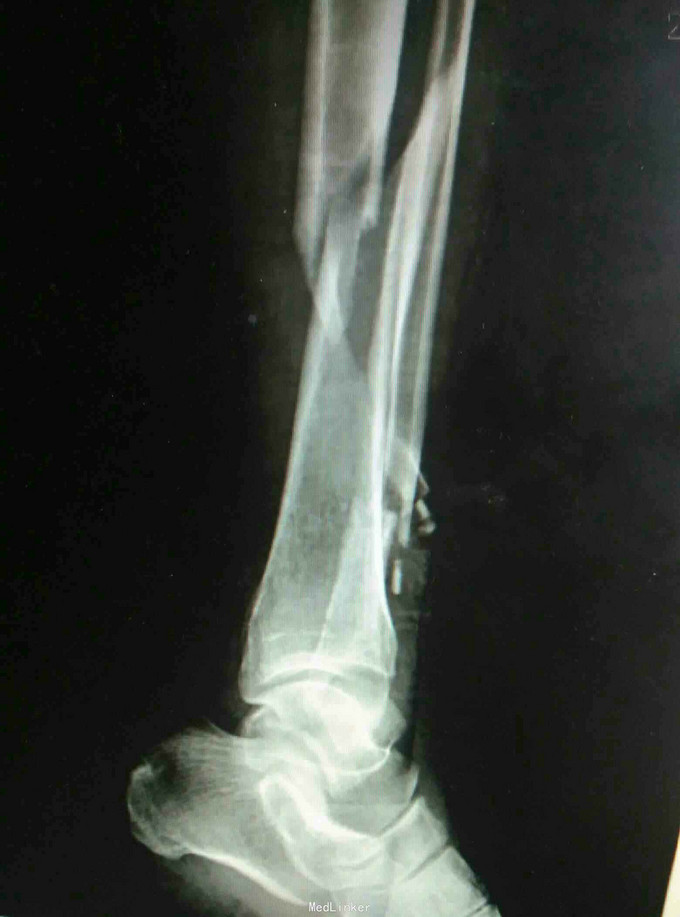

左小腿疼痛畸形,活动受限5小时 患者因骑车摔伤出现左小腿疼痛、畸形,当即出现活动受限无法站立,余未诉特殊不适,急诊摄片提示左胫腓骨远端骨折。

查体:左下肢肿胀畸形,局部可及骨擦感,压痛明显,未见明显张力性水泡,踝关节活动轻度受限,足趾感觉无异常,对侧膝踝关节活动无异常。 辅查:摄片提示左胫腓骨远端骨折。

诊断:左胫腓骨远端骨折 治疗:骨折切开复位内固定